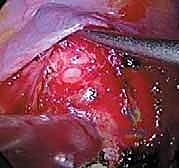

هذه العملية هي تحفة فنية هندسية وطبية. إليكم كيف يقوم الأستاذ الدكتور محمد هطيف وفريقه الجراحي المتميز بتنفيذها خطوة بخطوة في أفضل مستشفيات صنعاء المجهزة.

الخطوة 1: التخدير وتحديد الوضعية (Positioning)

يتلقى المريض تخديراً عاماً. يتم وضع المريض على جانبه (Lateral Decubitus Position) على طاولة عمليات خاصة تسمح باختراق الأشعة السينية. يتم تثبيت المريض بدقة شديدة لضمان عدم تحركه أثناء الإجراء.

الخطوة 2: المراقبة العصبية الفسيولوجية (Neuromonitoring)

هذه خطوة حاسمة لضمان الأمان. يتم توصيل أقطاب كهربائية بجسم المريض لمراقبة وظائف الحبل الشوكي والأعصاب بشكل لحظي (Real-time) طوال فترة الجراحة. أي تغيير في الإشارات العصبية ينبه الجراح فوراً، مما يجعل خطر الشلل شبه معدوم.

الخطوة 3: الشق الجراحي والوص